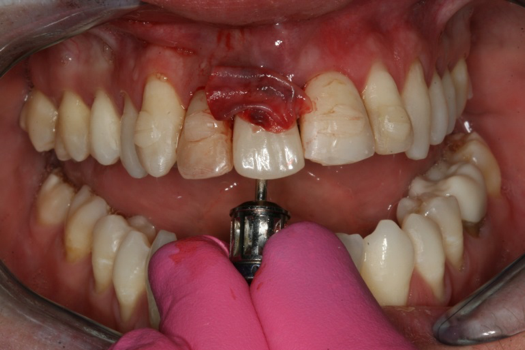

Fig 9. Surgery day with immediately loaded implant and treatment crown.

Figure 9

Figure 6 and Figure 7 depict a mature smile with many implant restorations. An analog impression was sent to the laboratory. The impression was scanned by the laboratory, a model was created virtually, and the implant dimensions and position were defined. The 3D surgical guide was fabricated (Figure 8), allowing the patient to receive his therapy swiftly and predictably. Tooth No. 8 was extracted, and the implant was placed and immediately loaded with an acrylic provisional treatment crown (Figure 9). The screw-retained treatment crown was fabricated in-office from a previously completed diagnostic wax-up.